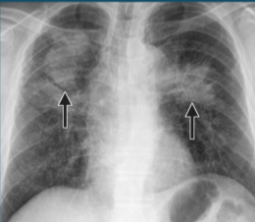

Ankylosing Spondylitis

diagnosis is confirmed by spine radiographs (especially of SI joints)

Bamboo Spine

Minor trauma → vertebral fractures

Aortic Regurgitation

Apical pulmonary fibrosis

Hilar Adenopathy